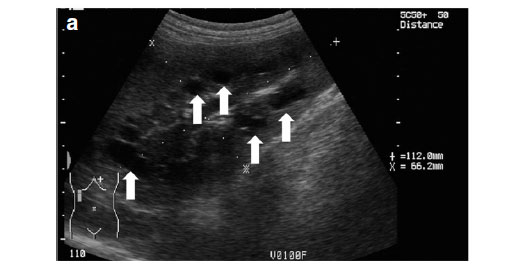

Abdominal ultrasonography was performed under sedation using medetomidine (Domitor, Pfizer, 1 mg/kg) at a dose of 10 µg/kg intravenously. The left kidney measured 10×6×7.5 cm with a slightly uneven margin (cranial pole was larger). A small amount of hypoechoic subcapsular fluid surrounded the kidney. Multiple round, well-marginated, anechoic, cystic structures were seen mainly in the medulla with some extending into the cortex. The largest of these measured 2.5 × 1.5 × 2 cm. These cysts had a clear edge shadow, distal acoustic enhancement with a thin but clear hyperechoic far wall (Fig. 2a,b). Some cysts contained multiple internal hyperechoic specks. The renal cortex was normoechoic and the corticomedullary junction was distinct. Two of the cranial pole cysts of the kidney were more hypoechoic and communicated with a large 5×3×3cm hypoechoic well-marginated, crescentshaped mass which distorted the cranial pole of the kidney. This structure had hyperechoic septa and multiple hyperechoic internal specks that swirled on ballotment. Acoustic enhancement and edge shadowing were seen. Slice thickness artefact was noted in the mass mimicking sediment. No gas was noted in the mass. The right kidney measured 11 × 6 × 5 cm. Multiple smaller (largest about 1×1×1.5 cm) anechoic structures were present mainly in the medulla (Fig. 3a,b). Some of these cysts communicated with each other and some had multiple hyperechoic internal specks. No cysts were found in any of the other abdominal organs, including the pancreas and the liver. The ultrasonographic diagnosis was atypical multiple renal cysts with a suspected large left renal cranial pole cortical abscess. Other individual complicated cysts could not be excluded. The differential diagnosis for cyst-like structures included uniform blood clots, unclotted blood, abscesses without debris, lymphomatous masses and necrosis related to tumours or cystadenocarcinomas35.